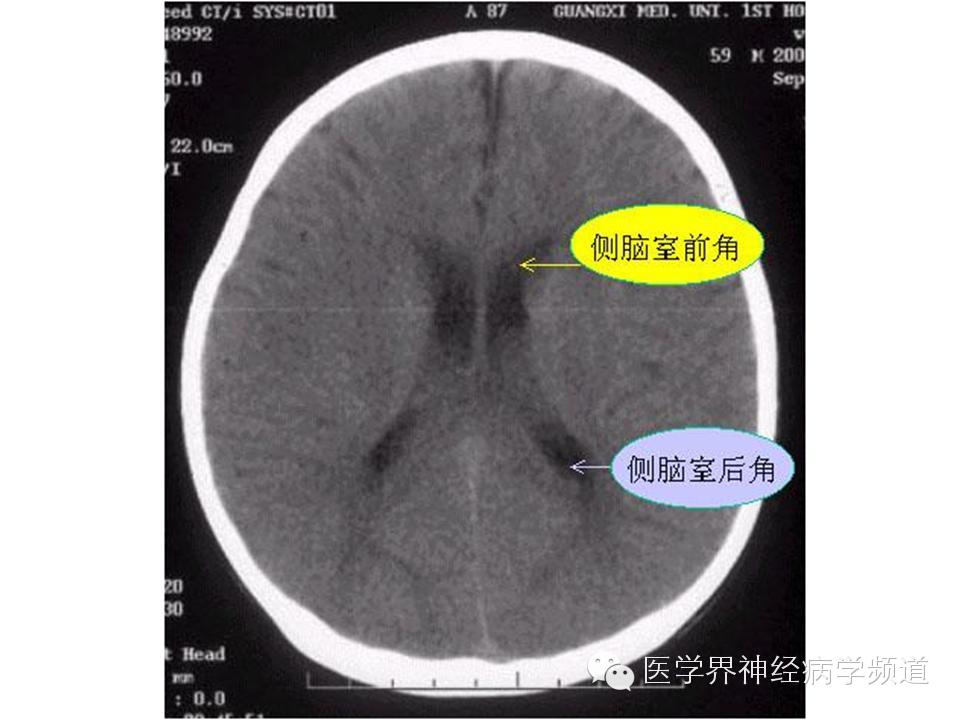

神经影像CT读片step by step